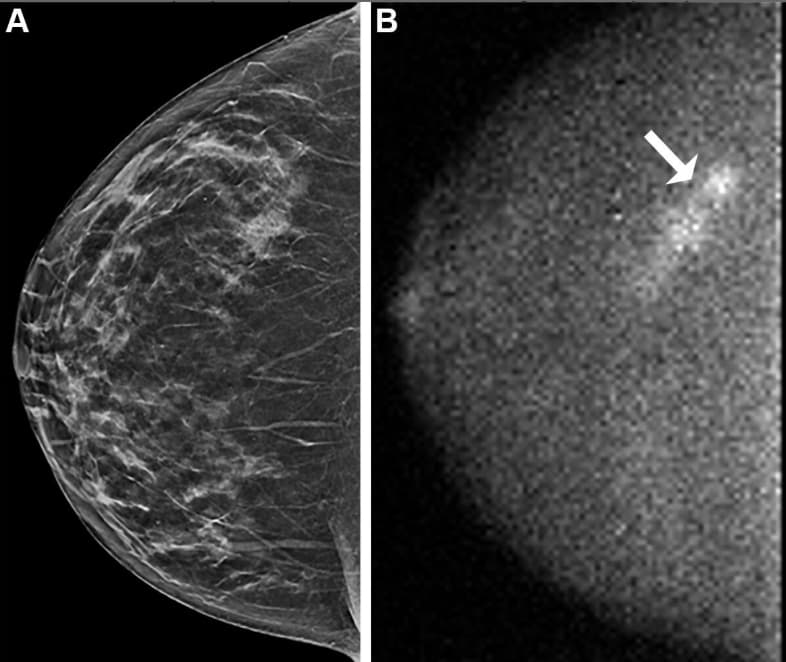

Une nouvelle étude plébiscite l'imagerie moléculaire en complément du dépistage du cancer du sein dense

Selon une nouvelle étude publiée dans la Revue Radiology, le dépistage du cancer du sein chez les femmes ayant une densité mammaire élevée peut être améliorée en combinant imagerie moléculaire du sein (MBI) et tomosynthèse. Cette combinaison a permis de détecter davantage de cancers invasifs, tout e...